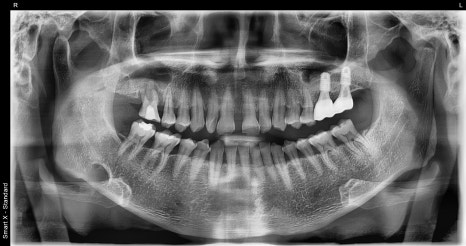

왼쪽 사진: 환자분 첫 내원 당시 파노라마 엑스레이 사진입니다.

오른쪽 사: 초기 구강 내 사진으로, 어금니 쪽 잇몸과 치아 상태를 보여줍니다.

맨 뒤 큰 어금니는 처음 내원 시부터 결손된 상태였고, 그 앞 어금니는 치근단 염증이 심한 상태였습니다.

또한 작은 어금니는 흔들림이 심해, 두 치아 모두 발치 후 임플란트로 대체하였고, 전체 잇몸 치료도 함께 병행하여 치료 계획을 수립했습니다.